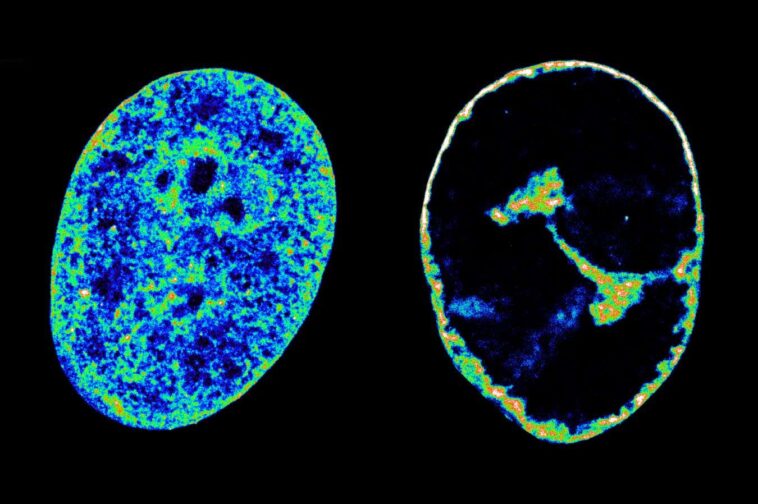

L'ADN humain dans son état naturel à l'intérieur des cellules (à gauche) par rapport à son état 8 heures après avoir été infecté par le virus du froid (à droite)

Des études antérieures ont montré que le génome humain devient plus étroitement enroulé pendant l'infection à HSV-1, ce qui peut perturber la fonction cellulaire, mais il n'était pas clair pourquoi cette enroulement se produit.

Mais ils ont également montré que ce vol est ce qui semble faire en sorte que l'ADN hôte se réunisse plus étroitement, ce qui le réduit à 30% de son volume de pré-infection dans les 8 heures suivant l'infection.